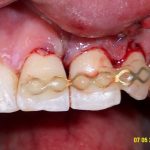

Sévère retrait gingival

Chirurgie avec greffe tissus conjonctif

Résultat à 3 mois